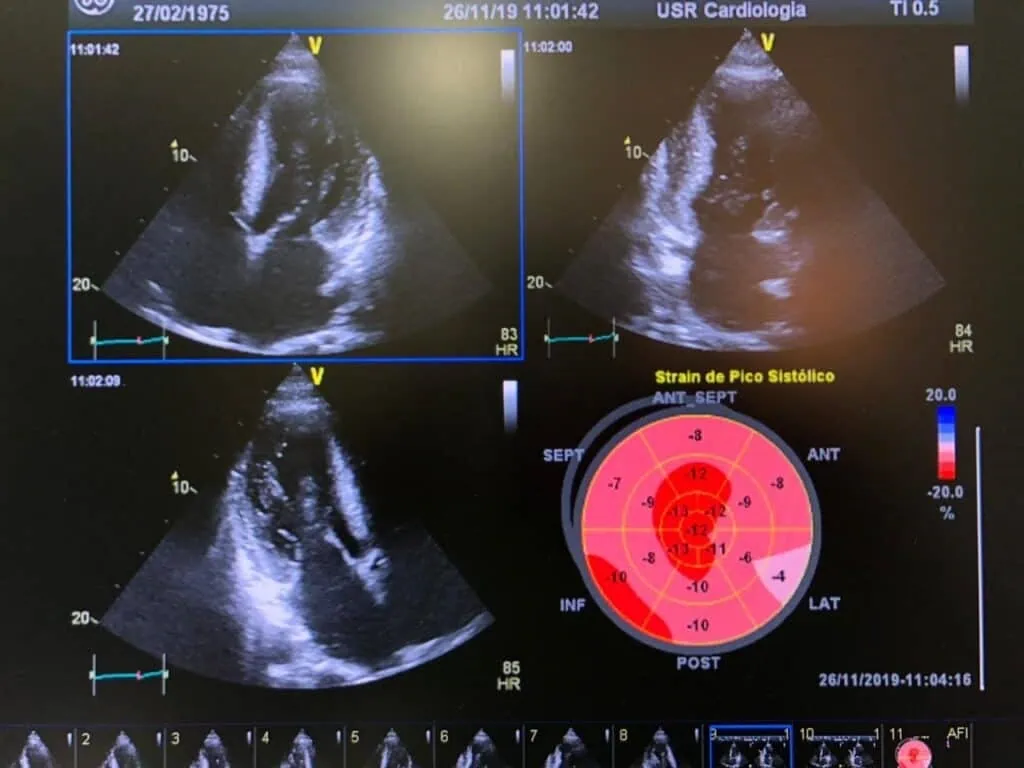

As novas tecnologias derivadas do Doppler tecidual colorido e da deformação longitudinal bidimensional (Global Longitudinal Strain), permitem a demonstração da presença de disfunção sistólica na amiloidose cardíaca mesmo quando ainda não pode ser avaliada pela ecocardiografia convencional, ou seja, mesmo quando a fração de ejeção ainda está normal e, além disso, também agrega valor prognóstico. Um valor de deformação longitudinal global (Global Longitudinal Strain) ≤ − 13 é o ponto de corte mais apropriado para predizer uma mortalidade maior. Ainda que a redução da deformação longitudinal na amiloidose cardíaca seja encontrada em todos os segmentos, ela é mais acentuada nos segmentos basais e mediais e isto se deve ao fato da torção ventricular estar reduzida por causa de uma alteração na rotação basal e medial do VE, enquanto a rotação apical se mantém normal. Alguns autores consideram que uma deformação longitudinal global inferior a − 12 na presença de espessamento parietal ventricular é bastante sugestiva de amiloidose cardíaca. A deformação bidimensional longitudinal global do ventrículo direito (VD) também apresenta nos segmentos basal e medial da parede lateral do VD valores diminuídos.

Global Longitudinal Strain: redução da deformação longitudinal encontrada em todos os segmentos, porém mais acentuada nos segmentos basais e mediais e relativamente preservada nos segmentos apicais.